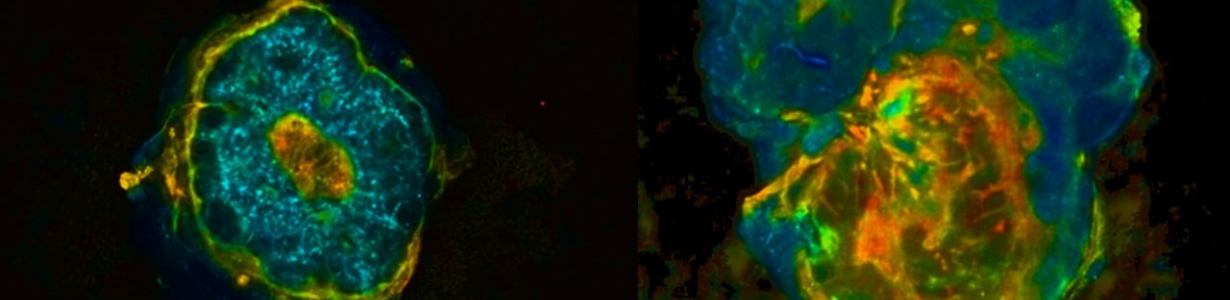

Суть метода в оптической экспресс-биопсии с использованием флуоресцентного макроимиджинга с временным разрешением. Эффективность технологии уже подтверждена на образцах 47 пациенток Нижегородского онкодиспансера с раком молочной железы.